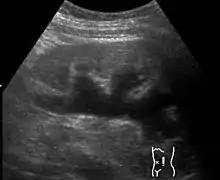

Renal ultrasonography of hydronephrosis caused by a left ureteral stone. | |

Imaging studies, such as an intravenous urogram (IVU), renal ultrasonography, CT, or MRI, are also important investigations in determining the presence and/ or cause of hydronephrosis. Whilst ultrasound allows for visualisation of the ureters and kidneys (and determine the presence of hydronephrosis and / or hydroureter), an IVU is useful for assessing the anatomical location of the obstruction. Antegrade or retrograde pyelography will show similar findings to an IVU but offer a therapeutic option as well. Real-time ultrasounds and Doppler ultrasound tests in association with vascular resistance testing helps determine how a given obstruction is effecting urinary functionality in hydronephrotic patients.[10]